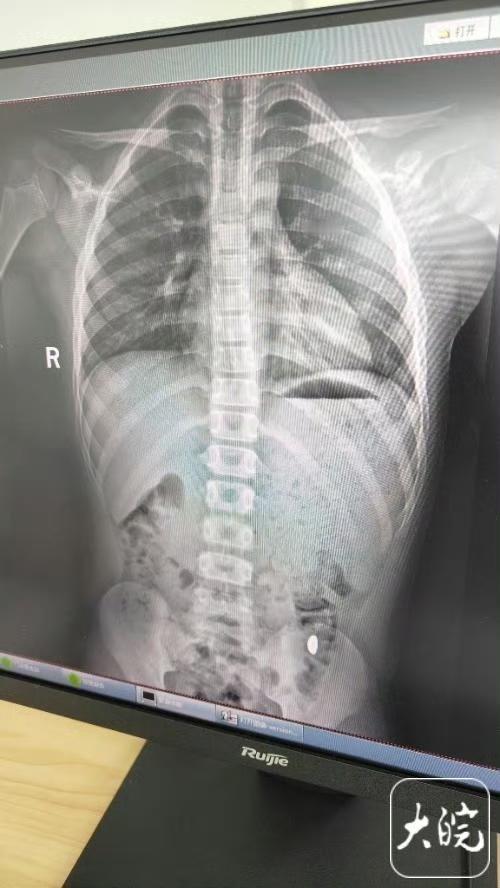

孩子误吞金豆,妈妈叮嘱别在外拉屎 事情发生在10月21日,纪女士花了一万元网购的金豆刚到货,儿子拿着玩说要“锻炼舌头力量”,结果一不留神就咽下去了。 孩子当时吓得大喊:“妈妈你快过来,我要死了!”纪女士一开始还以为是玩笑,后来想起亲戚家孩子吞过硬币,心里才咯噔一下。 但她没立刻去医院,反而天天叮嘱儿子“千万别在外面拉屎”,连着五天亲自检查粪便,可惜一直没找到金豆。 直到第六天,她终于坐不住了,带着孩子去医院拍CT,结果显示金豆还在胃里。 没想到当天下午,孩子在家上厕所时,金豆竟然自己排出来了。 说实话,这位妈妈的处理方式其实挺危险的。 医生后来提醒,误吞异物第一件事就该去医院检查位置,千万别自己硬扛。 尤其是电池、磁铁这类东西,分分钟可能造成肠穿孔。 不过万幸这次是黄金,性质稳定,加上孩子没什么不适,才没造成严重后果。 家长平时真的得把首饰、小零件收好,更要告诉孩子不能把东西往嘴里塞。 要是真遇到这种情况,冷静点,赶紧上医院——毕竟孩子的安全,可比什么都重要。